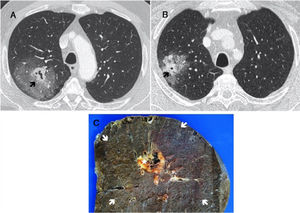

(A and B) Chest CT with IV contrast: lung window. Mass with central solid cavitary component (arrow) and extensive surrounding ground glass opacities. (C) Macroscopic specimen of lobectomy from case A, showing the central cavitary nodular lesion (star) surrounded by extensive perilesional hemorrhage (arrows) corresponding to the ground glass area on CT.

We report 2 cases of male patients aged 64 and 57 years, who consulted due to hemoptysis. Computed tomography showed pulmonary masses with similar radiological characteristics in the form of subsolid nodules with a central solid cavitary component and an extensive area of surrounding ground glass opacity (Fig. 1A and B). In the PET study, the solid component had more intense uptake (A: 8 SUV, B: 6.2 SUV) and the ground glass component had lower uptake (A: 2 SUV).

Transthoracic fine needle aspiration and biopsy (FNAB) was performed, accessing the peripheral part. The result showed hemorrhage and the pathology diagnosis of the surgical specimen was pleomorphic carcinoma of the lung with extensive peritumoral hemorrhage (Fig. 1C).